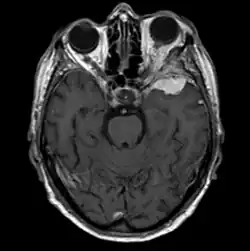

Sphenoid wing meningioma

A sphenoid wing meningioma is a benign brain tumor near the sphenoid bone.

Sphenoid wing meningiomas are diagnosed by the combination of suggestive symptoms from the history and physical and neuroimaging by magnetic resonance imaging (MRI) or computer averaged tomography (CT). Tumors growing in the inner wing (clinoidal) most often cause direct damage to the optic nerve leading especially to a decrease in visual acuity, progressive loss of color vision, defects in the field of vision (especially cecocentral), and an afferent pupillary defect. If the tumor continues to grow and push on the optic nerve, all vision will be lost in that eye as the nerve atrophies. Proptosis, or anterior displacement of the eye, and palpebral swelling may also occur when the tumor impinges on the cavernous sinus by blocking venous return and leading to congestion. Damage to cranial nerves in the cavernous sinus leads to diplopia. Cranial nerve VI is often the first affected, leading to diplopia with lateral gaze. If cranial nerve V-1 is damaged, the patient will have pain and altered sensation over the front and top of the head. Horner's syndrome may occur if nearby sympathetic fibers are involved.

Tumors found in the external third of the sphenoid are of two types: en-plaque and globoid meningiomas. En plaque meningiomas characteristically lead to slowly increasing proptosis with the eye angled downward. Much of this is due to reactive orbital hyperostosis. With invasion of the tumor into the orbit, diplopia is common. Patients with globoid meningiomas often present only with signs of increased intracranial pressure. This leads to various other symptoms including headache and a swollen optic disc. The differential diagnosis for sphenoid wing meningioma includes other types of tumors such as optic nerve sheath meningioma, cranial osteosarcoma, metastases, and also sarcoidosis. Following the physical exam, the diagnosis is confirmed with neuro-imaging. Either a head CT or MRI with contrast such as gadolinium is useful, as meningiomas often show homogenous enhancement. Angiography looking for signs like stretched arteries may be used to supplement evaluation of vascular involvement and to determine whether embolization would be helpful if surgery is being considered.